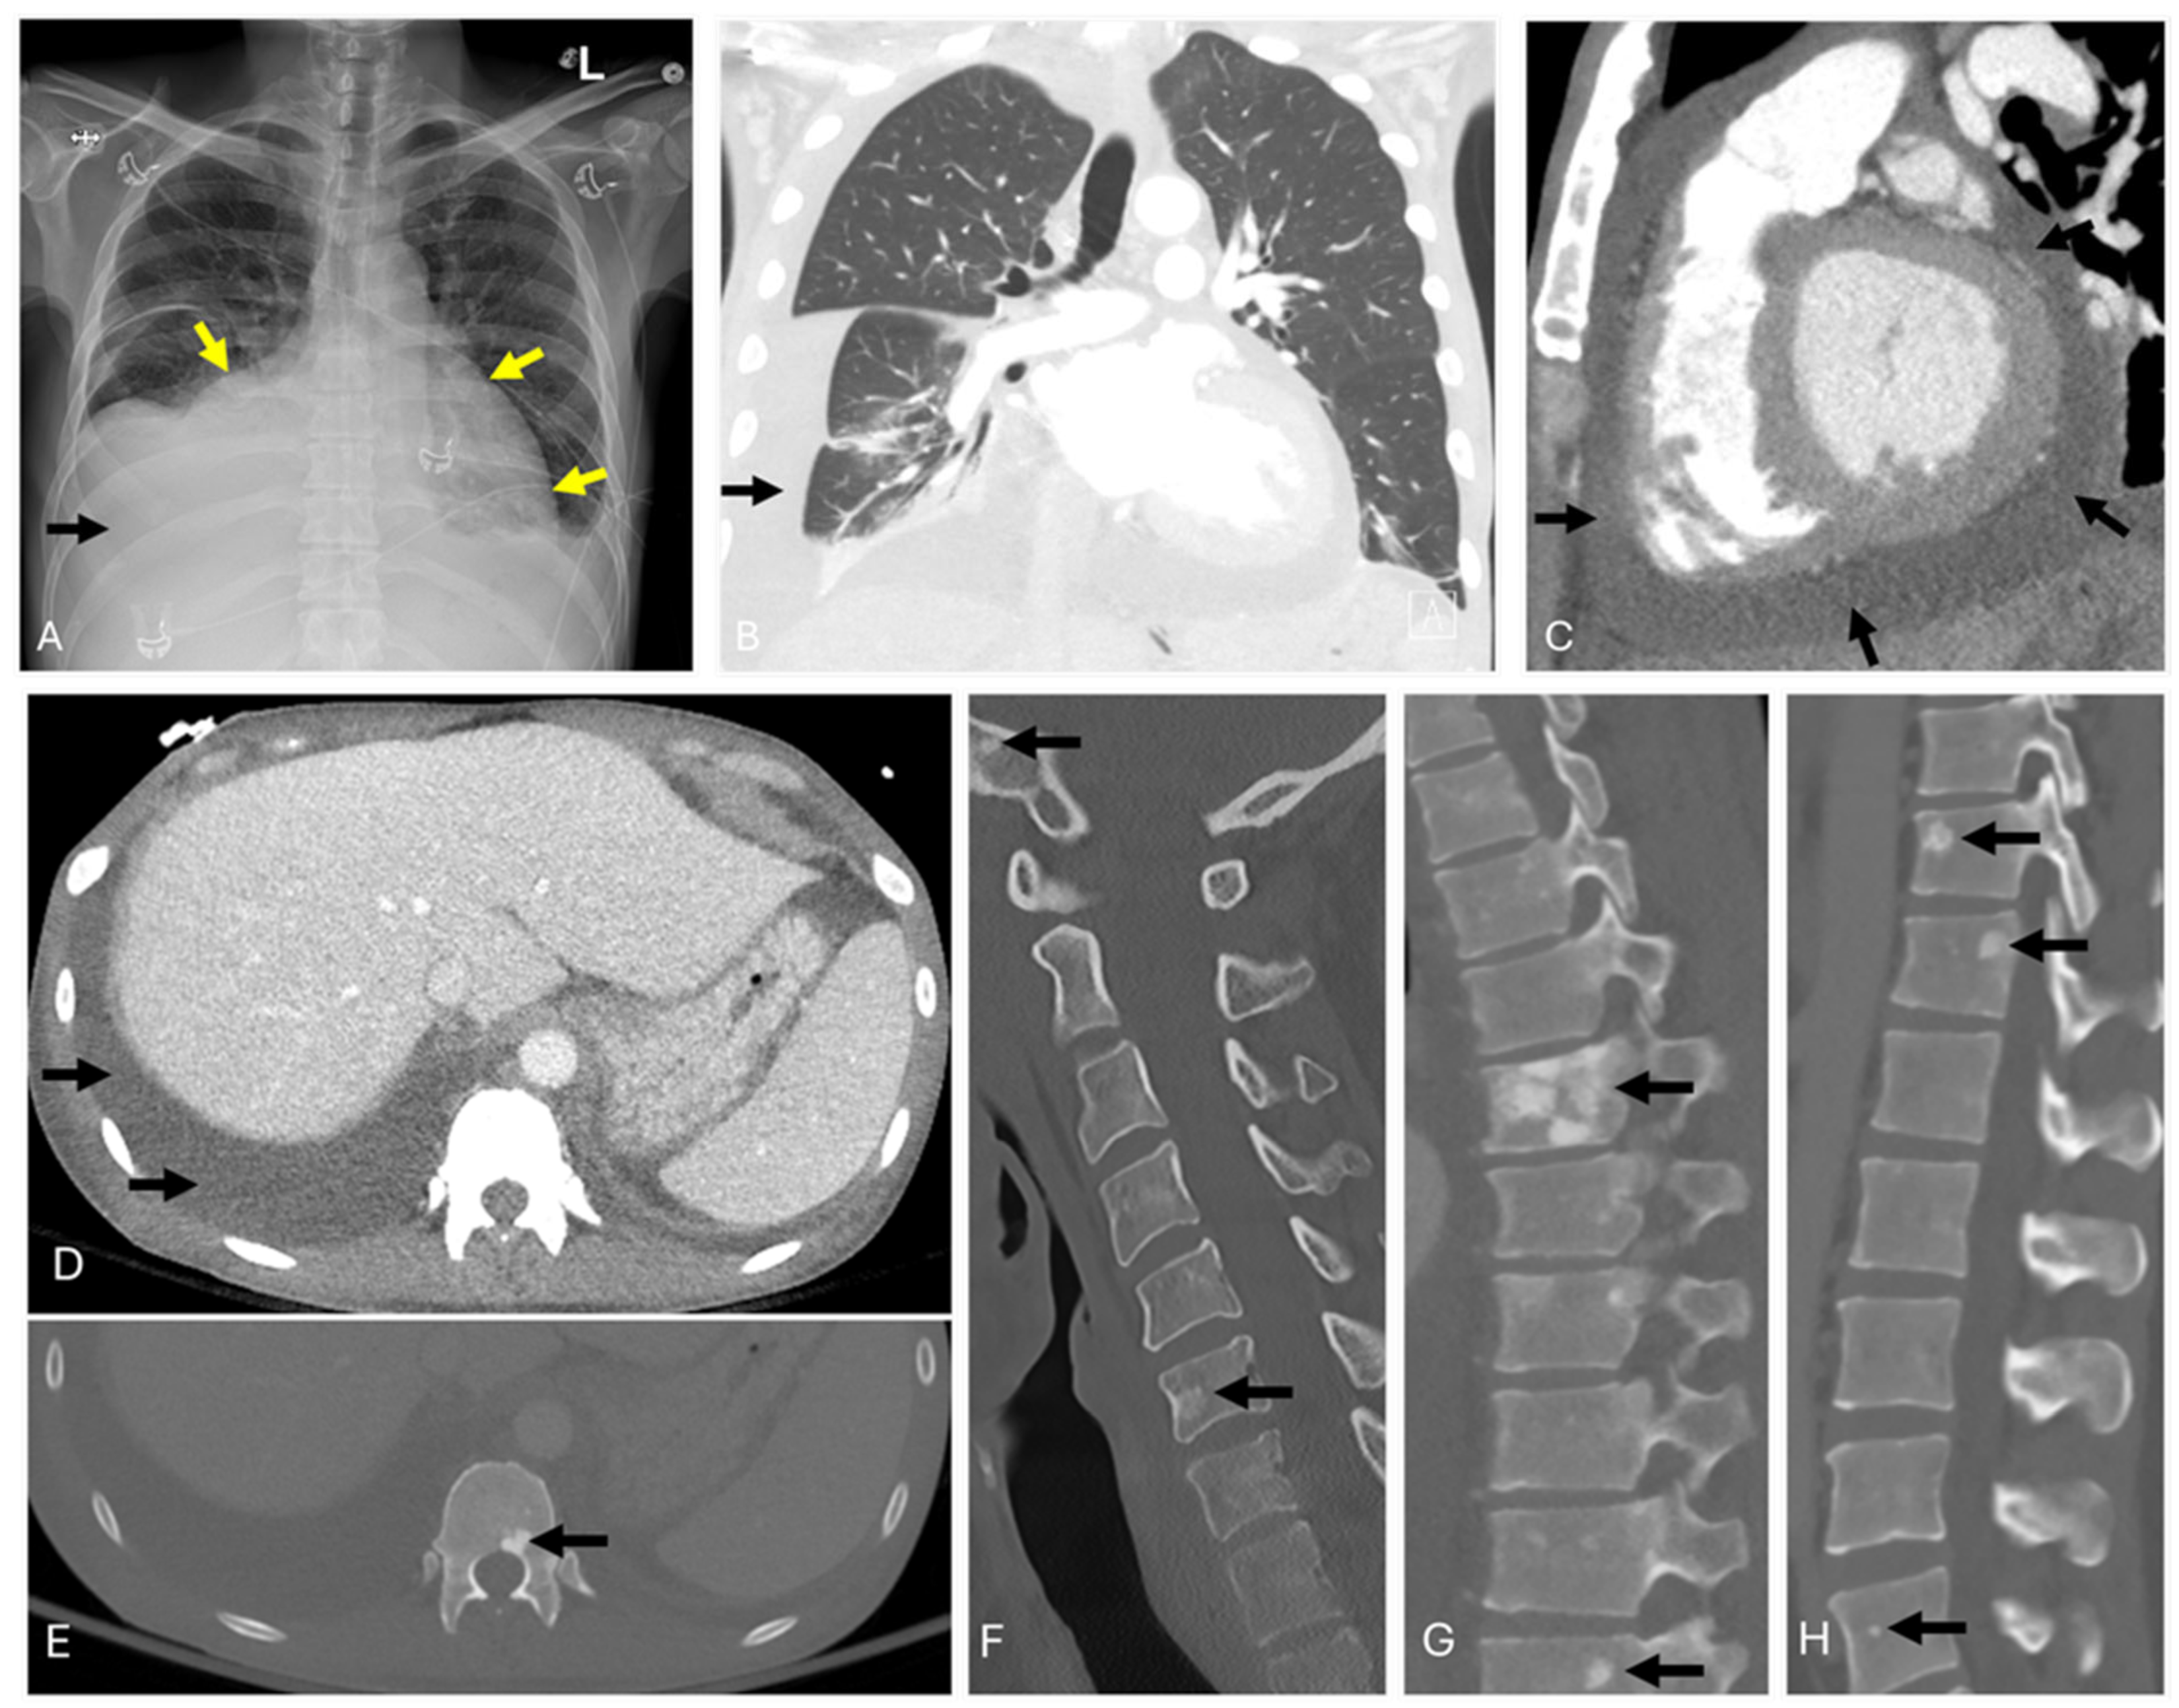

3.1. POEMS Syndrome

6. Imaging Considerations